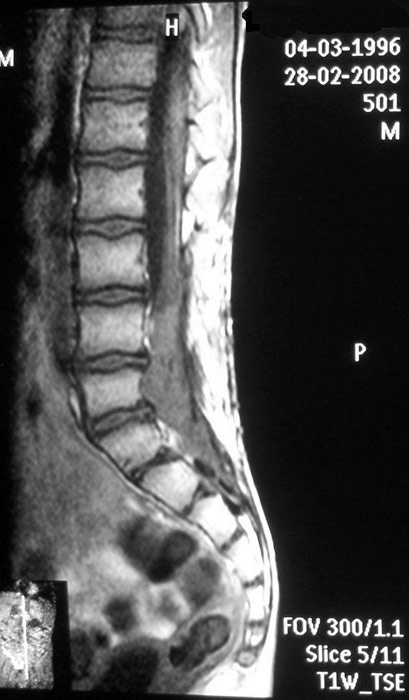

Спинальна магнітно-резонансна томографія (МРТ). Замість радіаційного випромінювання в МРТ використовуються потужні магнітні і радіохвилі для отримання зображення поперечного перерізу хребта. МРТ чітко відображає спинний мозок і нерви і забезпечує краще зображення пухлин кісток, ніж комп'ютерна томографія (КТ). Вам можуть ввести в вену кисті або передпліччя контрастну речовину, яка висвітлює деякі пухлини. Крім цього, використовують сканери з високою інтенсивністю сигналу для виявлення невеликих пухлин, які можна не помітити.